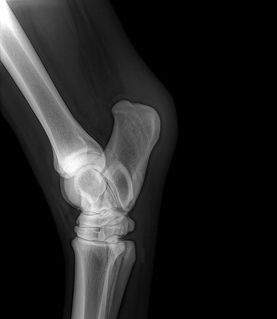

Digital radiography is used to view images of bone and soft tissue. The images are digital, rather than film and are available immediately, allowing for quick, on-site assessment of problems. The ability to manipulate the images on the computer and enhance specific regions of the image allows for better visualization of the problem areas.

Radiography is most commonly used in horses to view problems within the legs, making it an invaluable tool for lameness evaluations. Radiography is also very helpful in pre-purchase examinations, by helping uncover underlying or potential lameness issues before they manifest themselves symptomatically.